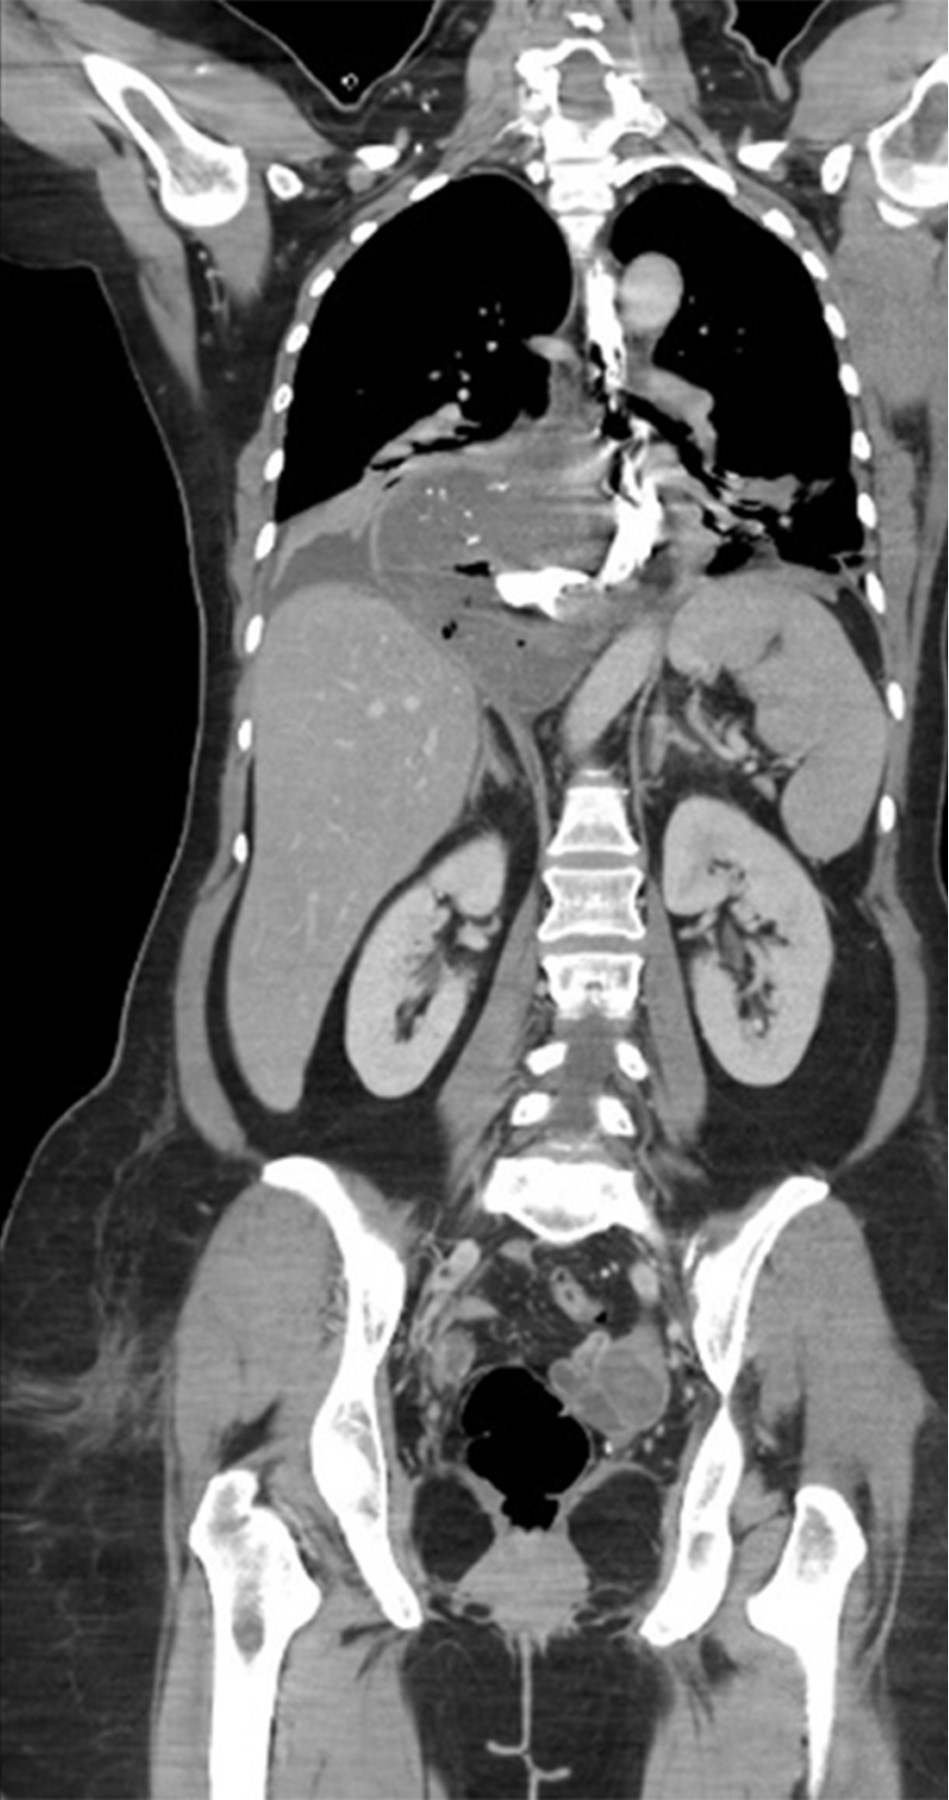

This is the case of a 54-year-old woman with a history of systemic arterial hypertension of 16 years of evolution in medical treatment with losartan 50 mg every 24 hours in reasonable control, history of total abdominal hysterectomy 14 years ago for uterine myomatosis, laparoscopic cholecystectomy four years ago for chronic calculous cholecystitis, both without apparent complications. She started with 36 hours of evolution with significant chest pain, unquantified fever, and attack to her general condition, so she came to our unit for evaluation. When specifically interrogated, she mentioned a history of five years of symptoms characterized by dysphagia to the ingestion of solid food. Physical examination revealed a patient in poor condition with tachycardia of 120 beats per minute, hypotension of 90/60 mmHg, respiratory rate of 23 breaths per minute, temperature of 36.5 °C, and generalized pallor of the integuments. The auscultation of the chest on the right side revealed decreased breath sounds with dullness to percussion. Her abdomen was flat, soft, and depressible with increased vocal vibrations, with no evidence of peritoneal irritation. Laboratory tests showed hemoglobin 16.6 g/dl, hematocrit 49.68%, white blood cells 18 cells/mm3, and neutrophils 89%. A thoracoabdominal tomography was performed, which showed a distal esophagus-dependent tumor associated with free fluid in the thorax and exit of contrast medium from the esophageal lumen (Figures 1 and 2). Due to the clinical picture of esophageal perforation and mediastinitis, it was decided to submit the patient to surgical treatment.

Imaging studies such as barium esophagogram, computerized tomography scan with oral contrast, esophagoscopy, and endoscopic ultrasound are helpful diagnostic tools in this pathology.17 In the present case, the thoracoabdominal tomography revealed a large tumor originating in the lower third of the esophagus, which after administering an oral contrast medium, showed a perforation of this organ, requiring emergency surgery.

Figure 1